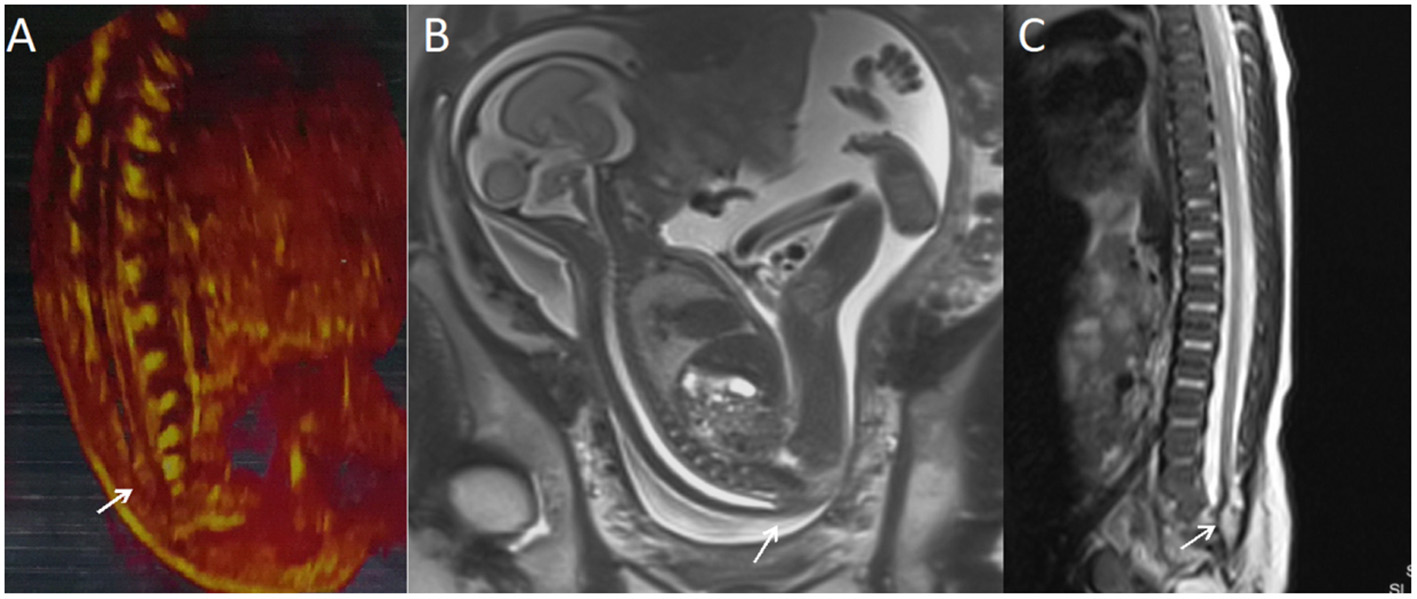

Figure 2

A fetus with intraspinal lipoma. (A) The prenatal ultrasound examination at 25 + 1 weeks of gestation showed the presence of low conus medullosus in the fetus and hyperechoic mass shadow in the spinal canal. Thus, intraspinal lipoma was considered. (B) Fetal magnetic resonance imaging (MRI) examination at 25 + 2 weeks of gestation showed the low conus medullosus of the fetus, with enlarged end of the conus medullosus and conus terminal and dural sac caudal adhesion. (C) T2 sagittal MRI of the lumbosacral vertebrae 20 days after birth suggested spina bifida and intraspinal lipoma.